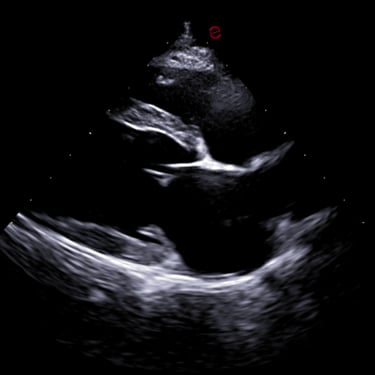

Dr. Hauer has completed over 270 formal hours of continuing education in diagnostic abdominal and cardiac ultrasound from a variety of experts in the field, including a year-long immersive Advanced Imaging program through the Academy of Veterinary Imaging in Arlington, TX. She is a member of the International Veterinary Ultrasound Society.

Sonopath SDEP Echo - (22 hours), 2022

Intermediate Echocardiography Course - Heska, 2023 (16 hours)

IVUSS International Veterinary Ultrasound Society - Advanced Cardiac Ultrasound/Advanced Diagnostic Ultrasound Lecture + Hands-on Laboratory Training (19 hours), 2025